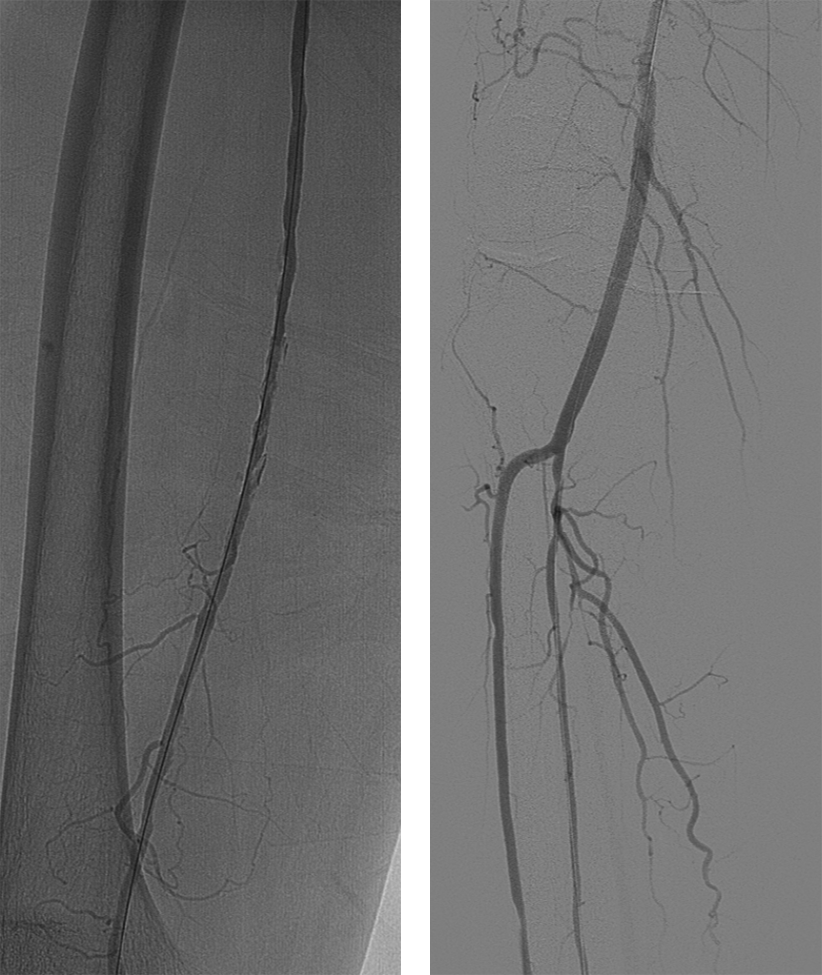

造影显示右侧髂外动脉、股动脉血栓栓塞。

Roterax吸栓后血流较前通畅,球囊扩张后局部夹层伴狭窄。

在狭窄端植入6mm*80mm Smartcontrol 支架1枚,造影显示血流通畅,予Exoseal 封堵穿刺点。